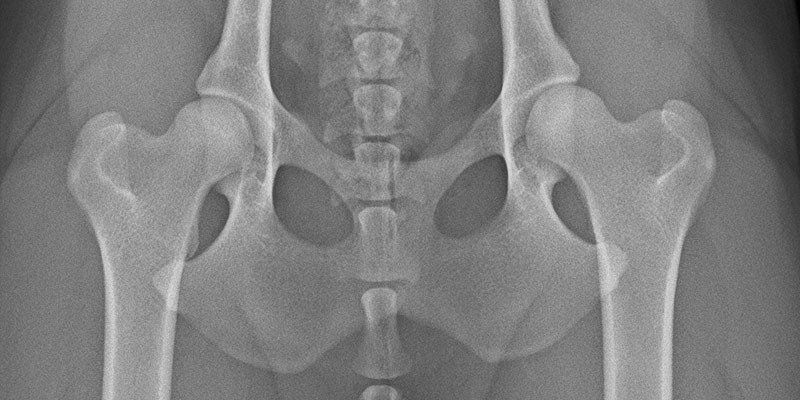

Die Hüftgelenksdysplasie ist eine angeborene Fehlentwicklung der Hüfte, bei der Oberschenkelkopf nicht passend in der Hüftpfanne sitzt. Entweder ist die Hüftpfanne zu flach oder der Oberschenkelkopf ist zu klein oder nicht rund genug.

Die Diagnose kann durch eine Röntgenunterschuchung in Narkose gestellt werden. Nur so können die Beine und die Hüfte korrekt gelagert werden.

Die HD lässt sich in die fünf Schweregrade A - E aufteilen. Ein Hund mit einer A-Hüfte ist HD frei, wohingegen ein Hund mit einer E-Hüfte eine schwere HD aufweist.